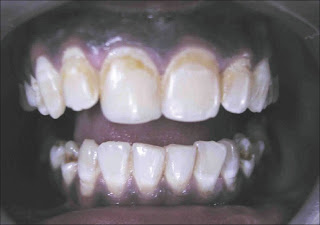

In case A, patient had mild grade of fluorosis and therefore in-office vital bleaching procedure with McInnes solution was advocated. McInnes solution has been successfully used for treating mild fluorosis. Advantage of this procedure is that it is relatively non-invasive compared to other restorative procedures and also it could be done with minimum chair side time. The main disadvantage of this procedure is the postoperative sensitivity it produces and that it cannot be employed in patients with more severe grade of fluorosis. [24] Vital bleaching is more successful for fluorosis in younger patients presenting with opaque to orange colour stain rather than older patients with darker type of brown stains. [25]